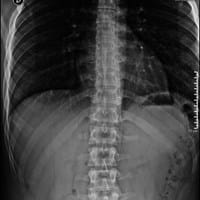

¿Qué debo hacer si tengo actitud escoliotica?

Hola comunidad tengo 18 años y hoy fui a mi traumatólogo y luego de haberme sacado una radiografía dorso lumbar de mi columna la cual adjunto en este link: Mi traumatólogo diagnosticó que no tengo escoliosis pero sí una pequeña desviación de 5.58...

Me llamo víctor tengo 18 años y hoy fui a mi traumatólogo y luego de haberme sacado una radiografía dorso lumbar de mi columna la cual adjunto en este link: Mi traumatólogo diagnosticó que no tenía escoliosis pero sí una pequeña desviación de 5.58...